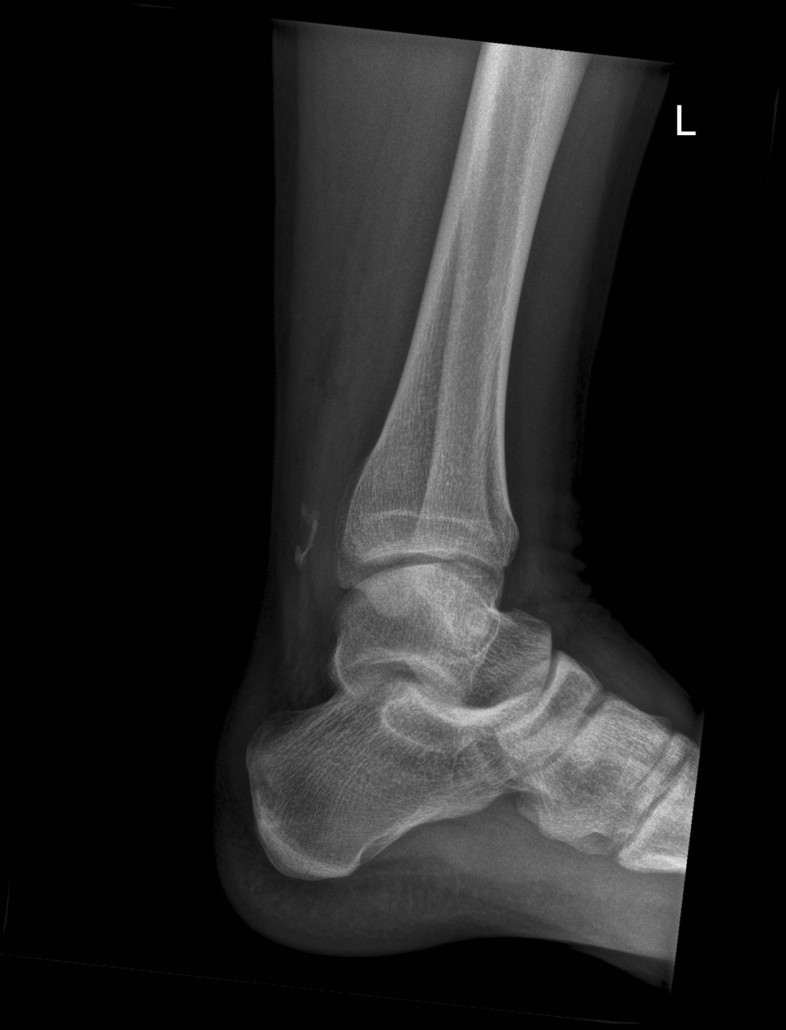

Ich hab recht schnell gemerkt, dass meine linke Ferse sich sehr komisch anfühlte und etwas weh tat. Einen Knall hab ich nicht gehört. Mein Mitfahrer ist dann zur Mittelstation abgefahren und hat die Pistenrettung alarmiert, die haben mich dann per Skidoo die 100 m zur Bergstation zurückgebracht. Von da gings per Gondel ins Tal und dann mit dem Rettungswagen nach Bludenz ins Landeskrankenhaus. Dort wurde ich abgetastet, geröntgt und dieser Test auf dem Bauch liegend gemacht, das Ergebnis war leider eindeutig, die linke Achillessehne ist durch. Morgen gehts zur Vorbesprechung nach Tettnang, übermorgen soll dann voraussichtlich operiert werden. Ich bin gespannt wie es weitergeht und hoffe, dass meine Genesung ohne Komplikationen abläuft und ich im Sommer wieder in den Bergen unterwegs sein kann.

Heute Voruntersuchung gehabt, die Sehne ist wie es aussieht nicht komplett durch, wird morgen dann operiert. Vacoped-Schuh ist bereits beim Sanitätshaus abgeholt...

Die OP ist gut verlaufen, scheinbar war die Sehne längs gerissen, was wohl eher untypisch sei.